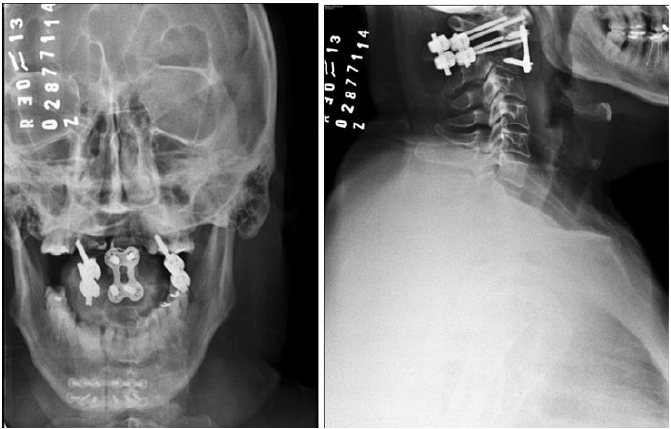

Computer Tomography was performed eight months after the last surgical intervention, evidencing the correct positioning of stabilization for both systems, besides the absence of radiological signs of relapse.

Five years after the surgical interventions, the patient keeps the same job with cross bite complaint and periodontal pain. Panoramic X-ray photographs were taken, the image suggesting generalized horizontal bone loss, yet without alterations in the plate and screws positioning in CII/CIII. Therefore, the patient has under gone dental follow-up (Figure 1-6).

Figure 6: Final RX.